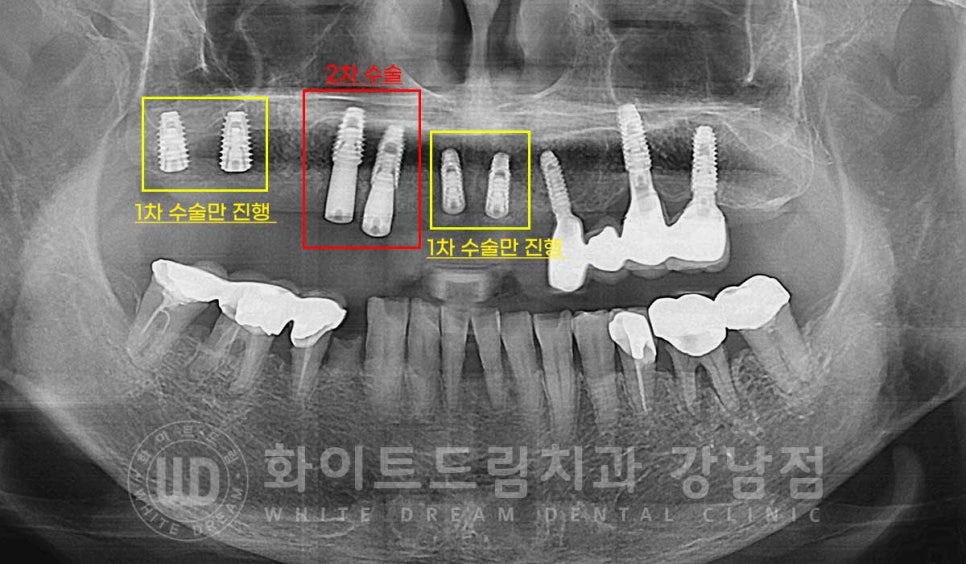

환자분의 당일 수술 후 x-ray 사진입니다.

상악 전체 임플란트 식립 후 / 수술 일자 : 23.08.10

식립된 임플란트를 보면 임플란트의 길이가 제각각인 것처럼 보이실 수 있습니다.

어떤 임플란트는 1차 수술만 진행하고, 어떤 임플란트는 2차 수술까지

진행했기 때문인데요.

자세히 보겠습니다.

초기 염증이 심했던 부위에 식립된 임플란트는 1차 수술만 진행했고

골질이 양호한 부위의 임플란트는 2차 수술까지 진행한 상태입니다.